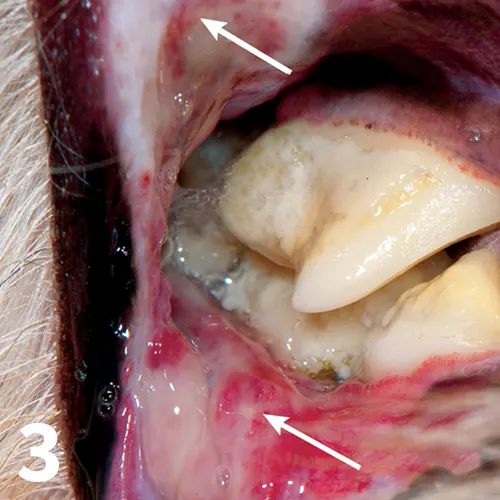

Figure 3

Swelling, ulceration, and marked inflammation (arrows) of the vestibular mucosa caused by plaque and tartar on the maxillary cheek teeth.

Examination is often difficult without general anesthesia; most affected patients experience significant pain on manipulation of the oral mucosa. In dogs and cats, the mucosa apical to the maxillary canines and fourth premolars are the most likely to be involved.4 They exhibit marked inflammation with or without ulceration and necrosis. In general, the vestibular mucosa in areas that contact tooth surfaces are also affected (Figure 3).